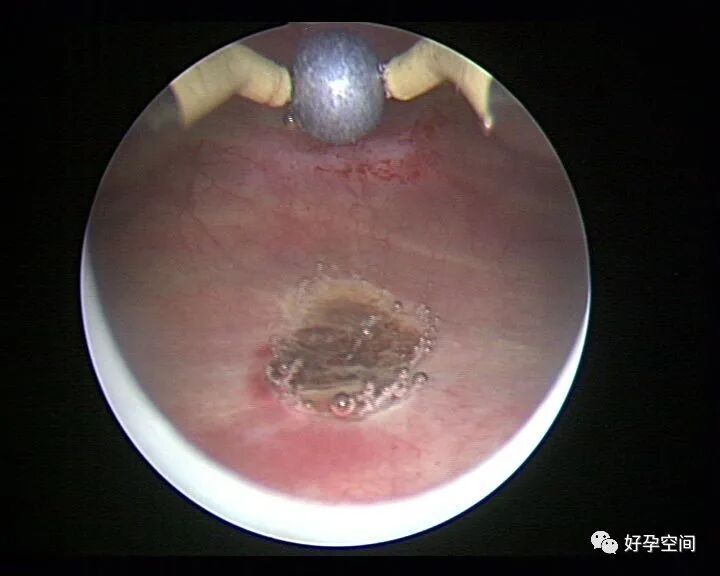

病例3:(病人年龄及取卵个数不详)取卵术后血尿膀胱内血块尿潴留,膀胱灌洗效果不佳,宫腔镜探查膀胱,清除血块,膀胱多处穿刺伤,电凝止血。

病例4:32岁,取卵13枚,取卵术后血尿膀胱内血块尿潴留,膀胱灌洗效果不佳,宫腔镜探查膀胱,清除血块,膀胱底见穿刺伤,电凝止血。